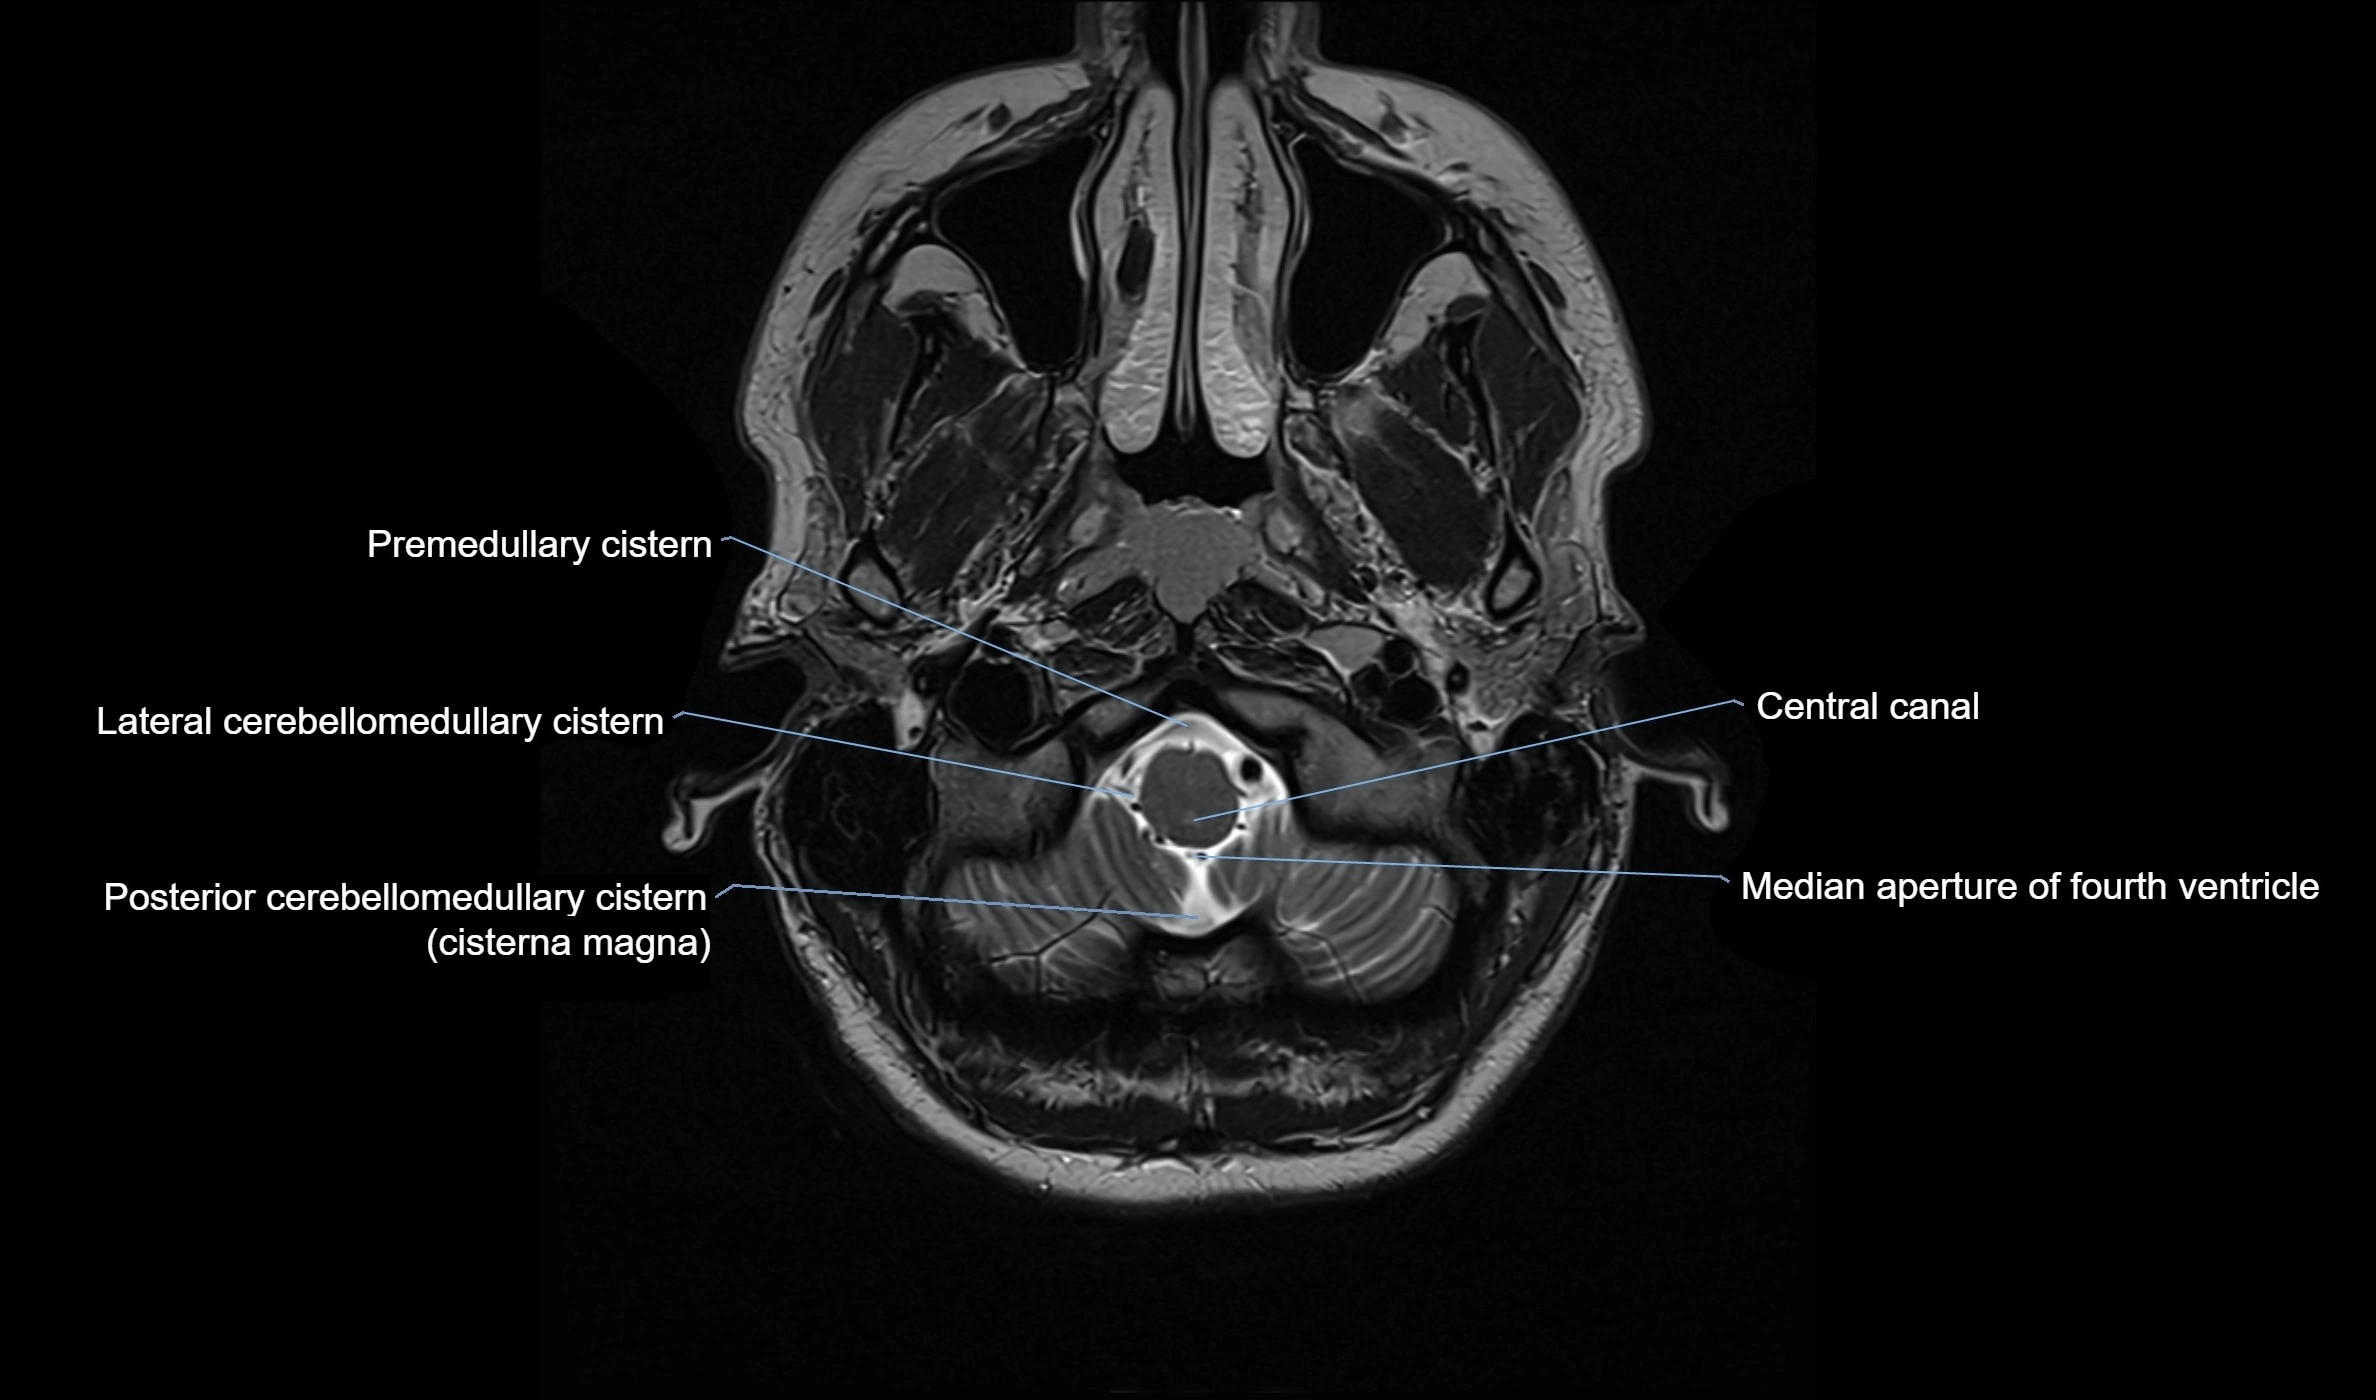

CT image

image